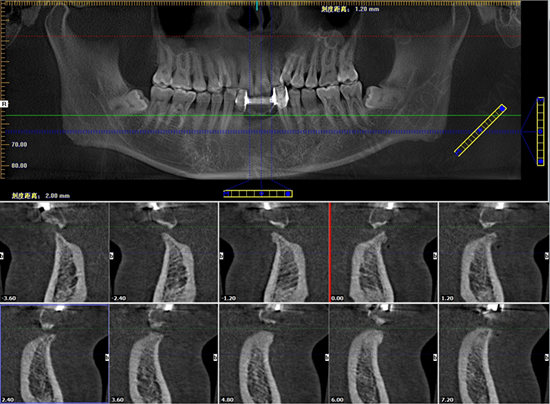

口腔全景片检查

冯海宏口腔全景片

在经过反复的分析诊断后,麦芽口腔种植医师团队为冯先生制定了麦芽MAC数字化精确种植牙修复方案,综合运用数字化3d导航、舒适种植技术,轻轻松松就解决了多颗牙缺失的问题,更避免了槽骨萎缩、无法进行传统种植的弊端,仅需一个小时就中上了新牙。